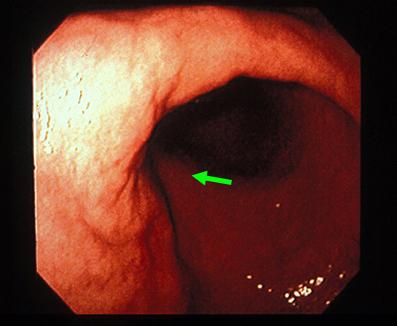

질환(병리주체)의 분류 악성 상피성종양/선암

부위(장기별) 위(부위)/2개 이상

검사방법 내시경

종양의 육안분류 4형(미만침윤형)/

종양의 최대경(밀리미터) 40이상

종양의 심달도 ss(a1)